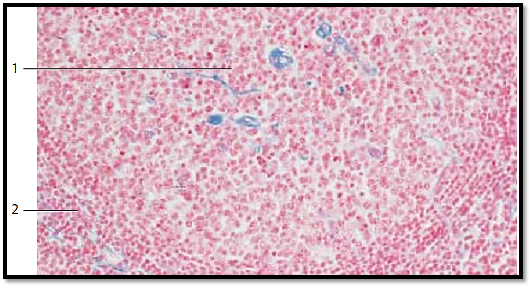

Outer zone of a human inguinal lymph node. The marginal sinus ( sinus marginalis) wraps around the lymph node immediately underneath the capsule 1 like a shell. Numerous afferent lymph vessels ( vasa afferentia) discharge into this marginal sinus. Reticulum cells with many cytoplasmic processes span the marginal sinus. Delicate collagen and reticulum fibers (here stained light blue) lend mechanic support to the cells. A follicle with many lymphocytes (a lymphatic nodule ) 3 is shown in the lower half of the figure.

1 Capsule

2 Marginal sinus

3 Lymph follicle

Stain: azan; magnification: × 400